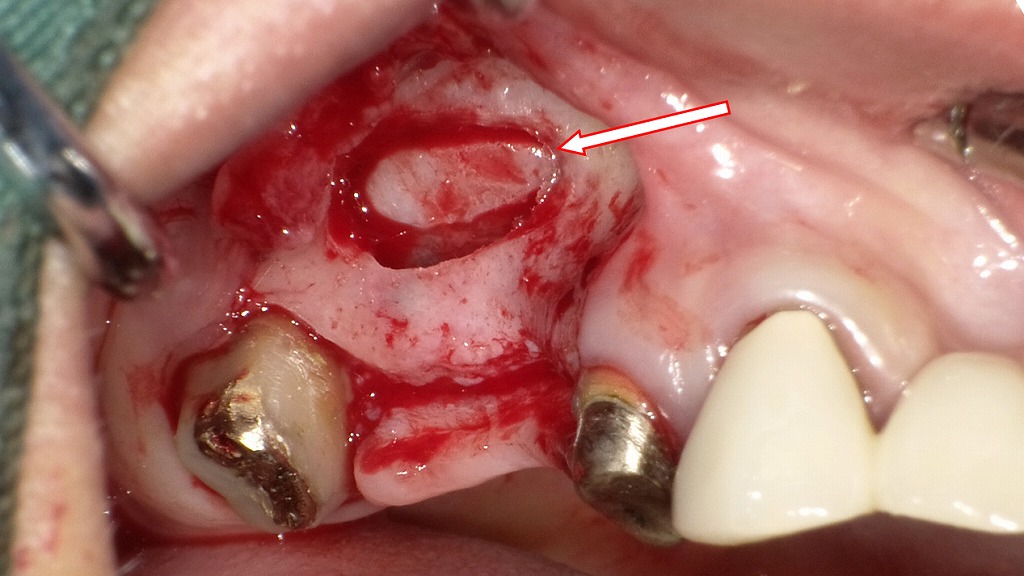

この画像は、上顎右側臼歯部でサイナスリフト術中の口腔内写真です。

🦷 手術部位の概要

- 対象部位:上顎右側4〜7番部(前回はブリッジで補綴されていた領域)

- 処置:4〜7番のブリッジ除去後、上顎洞底挙上術(サイナスリフト)を行うための開窓部が確認できます。

- 赤矢印の先が、上顎洞のシュナイダー膜(粘膜)を露出させた部位です。

🩺 処置内容の詳細

① ブリッジ除去

- 既存の4〜7番ブリッジを除去し、支台歯(4番・7番)の状態を確認。

- 5番・6番は欠損であり、この部分にインプラント埋入を予定。

② 開窓(ラテラルウィンドウ)形成

- 上顎洞外側壁の骨を楕円形に削除して開窓し、粘膜を慎重に剥離。

- 上顎洞底を挙上するためのスペースを確保しています。

- このとき粘膜(シュナイダー膜)を損傷しないことが重要です。

③ 骨造成(サイナスリフト)

- 挙上した空間内に**人工骨(β-TCPやハイドロキシアパタイトなど)**を充填し、骨量を増加させます。

- さらに、**CGF(Concentrated Growth Factors)**を併用して血液由来の成長因子を添加し、骨形成促進と治癒を促進します。

🧬 CGFの役割

- CGFは患者自身の血液から遠心分離して作成されるフィブリンゲルで、骨再生と軟組織治癒を促進します。

- 人工骨と混合、あるいは上部を覆う形で使用されることで、創傷の安定化と骨の成熟促進が期待されます。

💡 今後の流れ

- 約6か月の骨成熟期間を経て、インプラント埋入が可能になります。

- その後、上部構造(クラウン)を装着し、最終的に咀嚼機能を回復します。